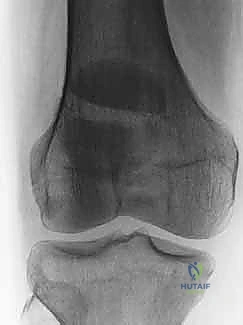

الأشعة السينية (X-rays): هي الخطوة الأولى والأساسية. يتم أخذ صور من زوايا متعددة:

- المنظر الأمامي الخلفي (AP View): لتقييم النمط العام للكسر.

- المنظر الجانبي (Lateral View): حاسم جداً لتقييم مدى تباعد أجزاء الكسر (Displacement) وعدم انتظام السطح المفصلي (Articular step-off).

تصنيف كسور الرضفة

يتم تصنيف كسور الرضفة بناءً على نمط الكسر ومدى تباعد الأجزاء العظمية. هذا التصنيف يوجه خطة العلاج.

| نوع الكسر (Fracture Type) | الوصف الطبي الدقيق | آلية الإصابة الشائعة | خطة العلاج المعتادة |

| الكسر المستعرض (Transverse) | كسر أفقي يقسم الرضفة إلى جزئين (علوي وسفلي). هو النوع الأكثر شيوعاً. | قوة شد عنيفة (انقباض العضلة الرباعية) أو ضربة مباشرة. | جراحي (ORIF) إذا كان هناك تباعد > 3 ملم، تحفظي إذا لم يكن هناك تباعد. |